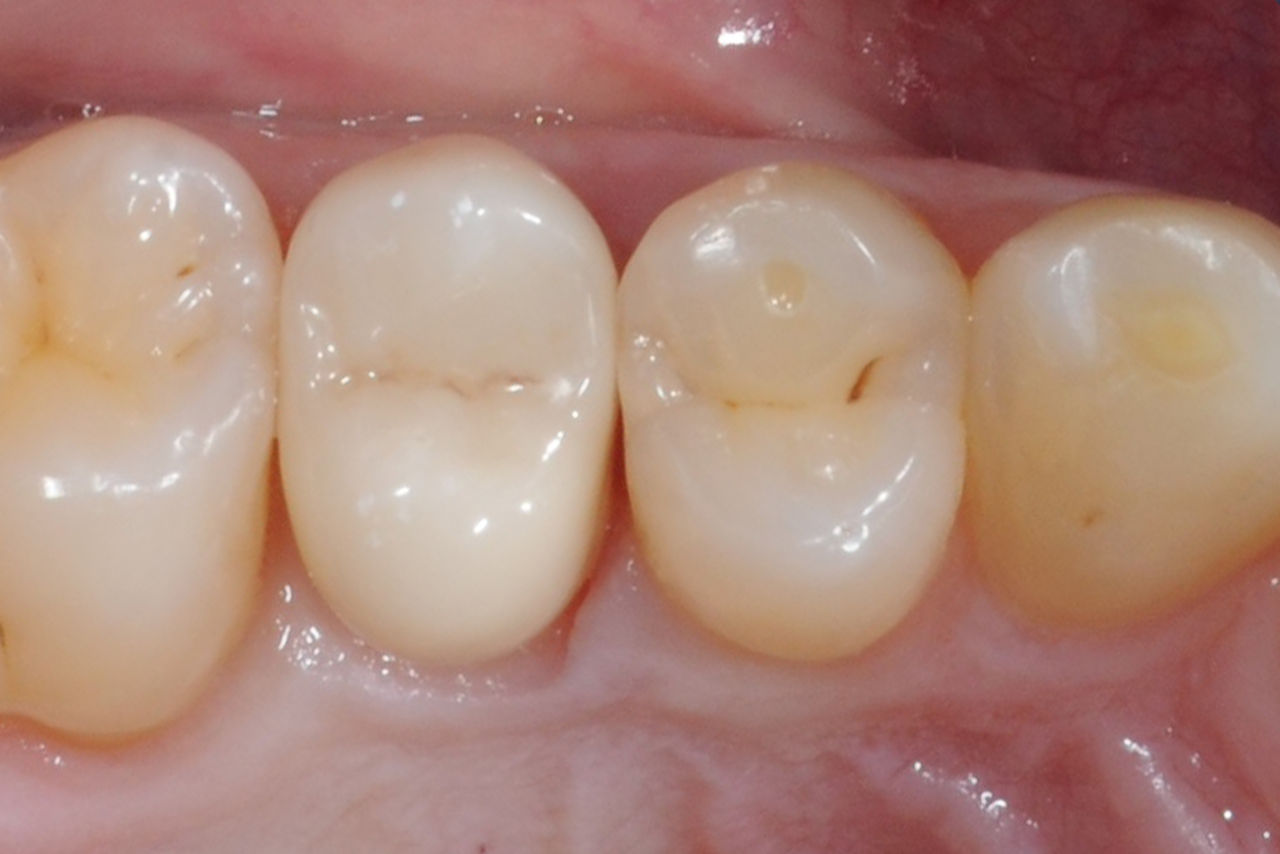

Primer molar superior en 60 minutos

Corona individual IPS.emax CAD

El caso clínico demuestra la rapidez y eficiencia con la que CEREC Primemill permite fabricar una corona de vitrocerámica de superficie completa chairside en una sola sesión, al mismo tiempo que cumple con las demandas estéticas más altas.

Antes: Insuficiencia grande del relleno de composite en el diente 16 con grietas marginales distales en la cresta, una grieta en la pared lingual y caries recurrente distal.

Después: Corona de vitrocerámica de superficie completa altamente estética.